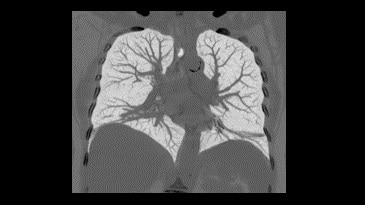

Vücut Görüntü Galerisi